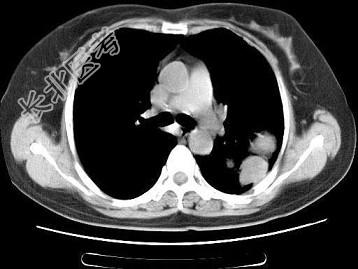

- 单项选择题女,52岁, 左侧背痛1月,胸部CT如图, 最可能的诊断为 ( )

A、左肺中央型肺癌

B、左肺周围型肺癌

C、左肺感染

D、左肺炎性假瘤

E、肺隔离征